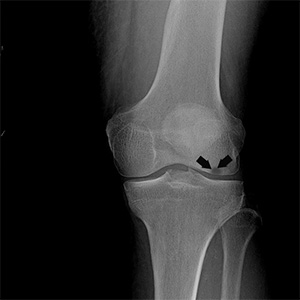

Knee Fracture

A fracture is a condition in which there is a break in the continuity of the bone. In younger individuals, these fractures are caused by high energy injuries, as from a motor vehicle accident. In older people, the most common cause is a weak and fragile bone.